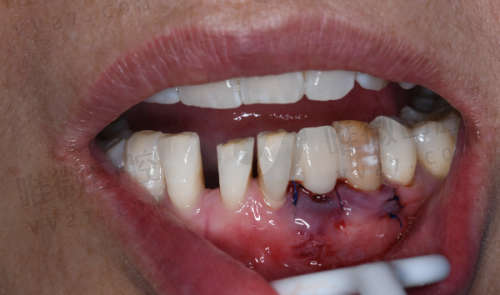

拔牙:49 - 580(包括儿童乳牙、智齿等不同复杂程度)